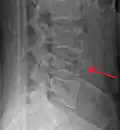

A burst fracture of L4 as seen one plane X ray A burst fracture of L4 as seen one plane X ray